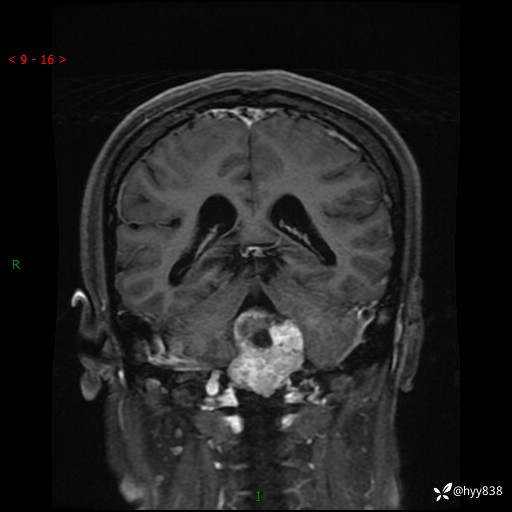

性别:女

年龄:47岁

简要病史:头晕1年余,间断恶心不伴呕吐

颅脑MRI平扫+DWI

增强(axi+cor+sag)

轴内、轴外占位

病灶的影像特征

轴内或轴外肿瘤